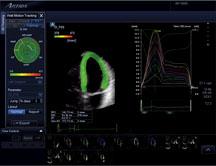

Since the introduction of cardiac ultrasound, investigators have sought to quantify cardiac function in three dimensions. The recent development of a new technology called 3D wall motion tracking (3DWMT), which displays quantitative echo data from 3D ultrasound data sets, has tremendous potential to more accurately evaluate ventricular function in a wide variety of cardiovascular diseases.